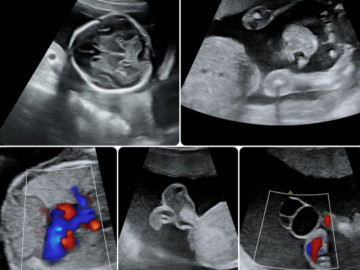

Mặc dù vậy, khó khăn của vợ chồng Sài thành chưa dừng tại đó. Suốt thai kỳ dù bầu bí suôn sẻ nhưng mỗi lần khám thai định kỳ là thai nhi trong bụng lúc nào cũng bị nhỏ hơn so với tuổi thai. Qua siêu âm, bác sĩ Trung còn phát hiện dây rốn bám màng bánh nhau - một trong những nguyên nhân gây thai nhẹ cân.

“Bác sĩ phát hiện dây rốn bám màng sớm sẽ giúp chủ động và kịp thời trong việc lên phương án theo dõi thai phù hợp và chuẩn bị các tình huống xử lý cấp cứu trong tình trạng khẩn cấp. Dây rốn bám màng có thể được chẩn đoán dựa trên hình ảnh siêu âm của nhau thai và dây rốn trong tam cá nguyệt thứ hai và thứ ba. Ở những thai phụ có dây rốn bám màng này nên được kiểm tra thường xuyên hơn vì nguy cơ đứt dây nhau có thể xảy ra ngay khi thai phụ có những cơn co tử cung đầu tiên”, bác sĩ Trung khuyến cáo.